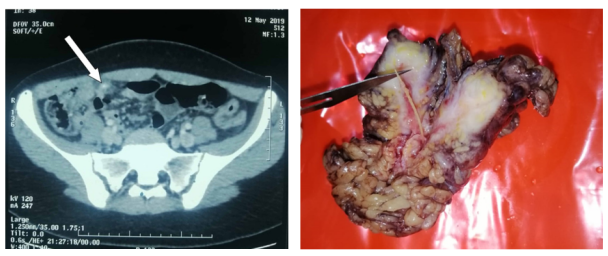

实验室检查显示C反应蛋白升高,白细胞计数正常。Alvarado评分为6/10,腹部超声显示阑尾扩张伴阑尾壁增厚6.5mm,并伴有线状异物。因此,进行了对比增强CT扫描,发现了急性阑尾炎的证据,以及自发性高密度线性图像的存在,长度为3cm(图1)。患者否认在两周内吞食过任何异物。

患者接受了开腹手术,显示阑尾发炎,网膜肉芽肿内有鱼骨。进行阑尾切除术,沿着鱼骨切除网膜肉芽肿(图2)。未发现胃肠穿孔的迹象。患者恢复顺利,于术后第2天出院。

图1. 腹部轴位增强CT显示阑尾扩张伴阑尾壁增厚,提示急性阑尾炎,并显示3厘米长的线性自发高密度图像(白色箭头)

图2. 标本显示鱼骨周围有网膜肉芽肿